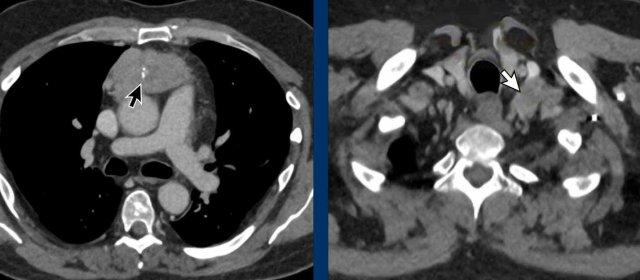

Ở trẻ sơ sinh, tuyến ức có thể khá lớn, đặc biệt khi có suy hô hấp, và có thể biểu hiện trên X-quang ngực với dấu hiệu cánh buồm (mũi tên đen).

Dấu hiệu cánh buồm tuyến ức là một phát hiện bình thường ở trẻ nhũ nhi và không nên nhầm lẫn với dấu hiệu cánh buồm thuyền, trong đó thùy tuyến ức bị đẩy ra ngoài và lên trên do tràn khí trung thất (mũi tên trắng).